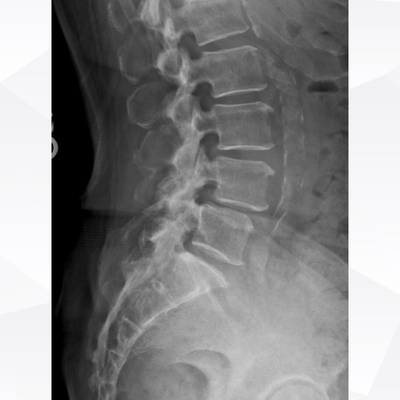

Click on an image below to view more info.